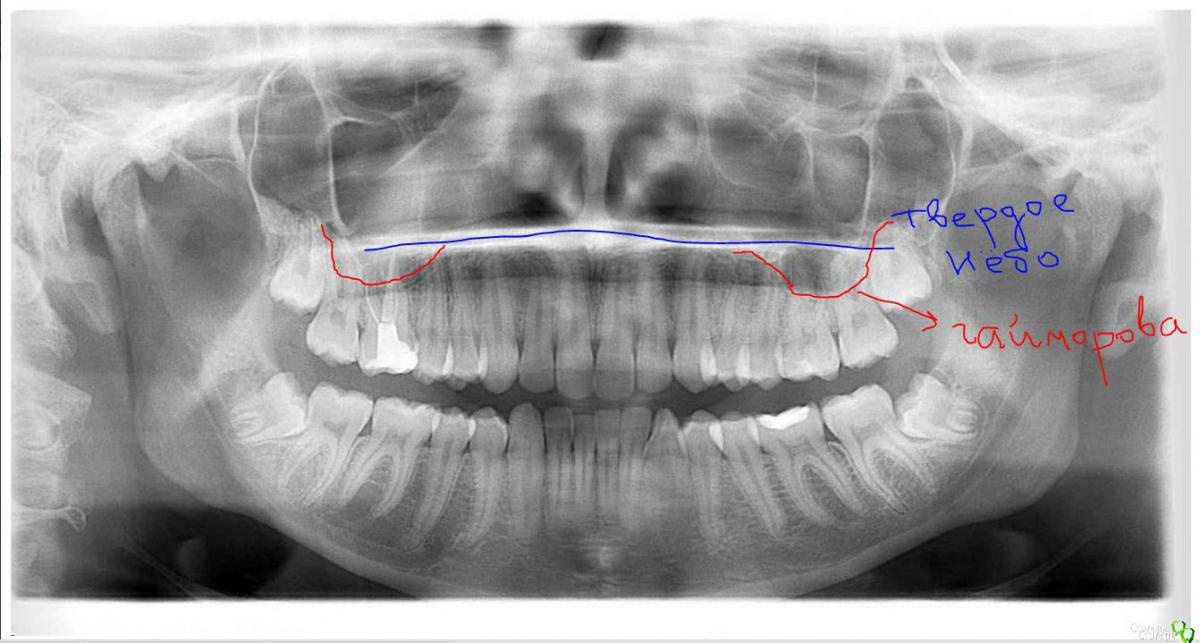

Orhan_dentist125 Опубликовано 11 марта, 2015 Поделиться Опубликовано 11 марта, 2015 ДД, коллеги. Видна ли на этом снимке киста 16 зуба?И что изображено над 26 и 27 зубом? Заранее спасибо Ссылка на комментарий

сирена Опубликовано 11 марта, 2015 Поделиться Опубликовано 11 марта, 2015 1.Не вижу2.Гайморова пазуха 1 Ссылка на комментарий

Orhan_dentist125 Опубликовано 11 марта, 2015 Автор Поделиться Опубликовано 11 марта, 2015 1.Не вижу2.Гайморова пазухаГайморову вижу, я про верхушки корней 26 и 27 говорю. Там вон границы хорошо видны Ссылка на комментарий

Чертков Александр Опубликовано 11 марта, 2015 Поделиться Опубликовано 11 марта, 2015 На верхушках корней 26 и 27Кроме бухты синуса ничего не вижу Ссылка на комментарий

marialera Опубликовано 11 марта, 2015 Поделиться Опубликовано 11 марта, 2015 над 17 есть деструкция Ссылка на комментарий

St. Опубликовано 11 марта, 2015 Поделиться Опубликовано 11 марта, 2015 Я патологии не вижу. По-моему как-то так.. 1 Ссылка на комментарий